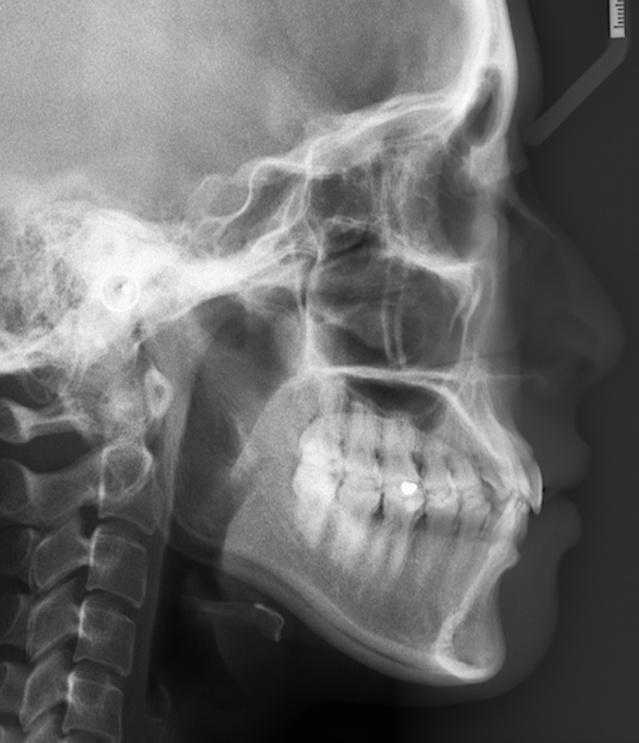

首先,我们需要明确的是,判断自己的龅牙属于牙性还是骨性,一定是需要结合头影侧位片来测量分析的,因为X光片更能直观反应出你的牙齿状况,单凭照片和网上的几招自测是无法确诊的。(这也是笑盈会让大家去我们的线下合作诊所拍口腔资料的原因)

下图看不懂吧?看不懂就对了。。